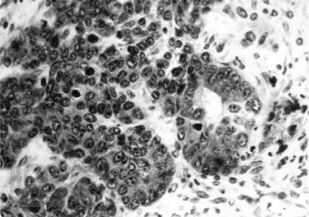

Книга посвящена описанию животных моделей in vivo для отбора, углубленного и/или доклинического изучения цитостатиков, а также некоторых таргетных средств. Представлены основные биологические характеристики, дополненные лекарственной чувствительностью и востребованностью в настоящее время.